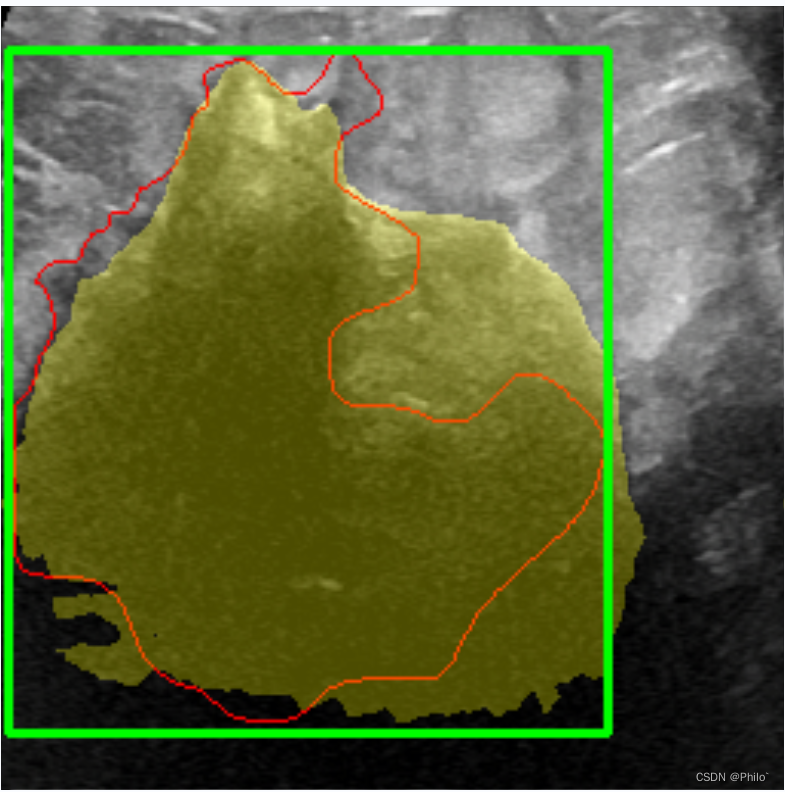

近年来,深度学习已被广泛用于乳腺癌的诊断中,并且出现了许多高性能模型。但是,大多数现有的深度学习模型主要基于静态乳房超声(US)图像。在实际诊断过程中,对比增强超声(CEU)是放射科医生常用的技术。与静态乳房图像相比,CEUS视频可以提供更详细的肿瘤血液供应信息,因此可以帮助放射学家进行更准确的诊断。在本文中,我们提出了一个基于CEUS视频的新型诊断模型。该模型的骨干是一个3D卷积神经网络。更具体地说,我们注意到放射线医生在浏览CEUS视频时通常遵循两种特定模式。